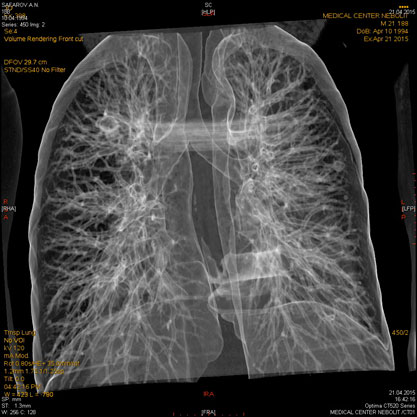

Современная МСКТ является методом объемного исследования всех областей тела человека, позволяет сканировать одну и более анатомических областей за один период задержки дыхания. Быстрота исследования является одним из главных преимуществ метода современной мультиспиральной компьютерной томографии, что обеспечивает уменьшение артефактов от движения, а широкие возможности постпроцессорной обработки изображений позволяют повысить точность исследования и сделать результаты максимально наглядными и точными.

- Трехмерная объемная реконструкция

МСКТ органов грудной клетки (легких и средостения).Рентген является базовым методом исследования грудной клетки. МСКТ применяется в выявлении стадии рака легкого, туберкулеза, определяет структуру патологических образований, таких как киста, солидный компонент, сосудистые, жидкостные и воздушные полости, подозрение на ТЭЛА.

С появлением МСКТ уходит в прошлое КТ с высоким разрешением для диагностики интерстициальных заболеваний легких. При использовании МСКТ можно дифференцировать диффузные интерстициальные процессы в легких альвеолит, бронхиолит, саркоидоз, канцироматоз и очаговые изменения.